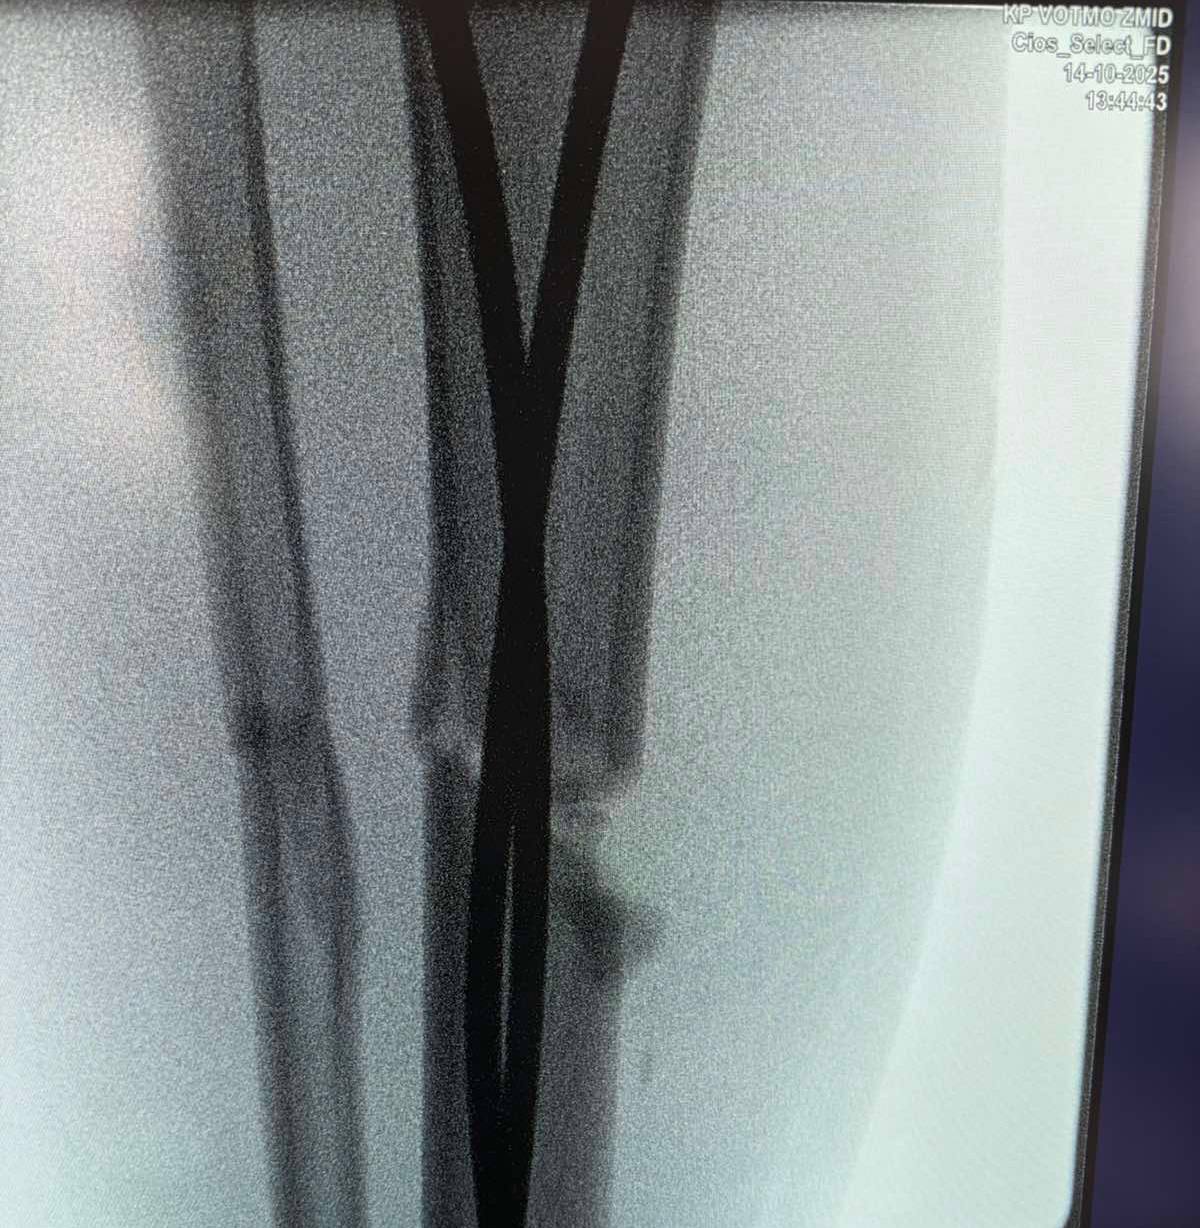

Оперативне втручання проводиться під рентген-контролем. Лікарі ортопедо-травматологічного відділення обласної дитячої лікарні застосовують інтрамедулярний остеосинтез вже понад 10 років.

Наслідки падіння для 13-річного Максима — перелом стегнової кістки зі зміщенням і кісток гомілки.

«Переломи дуже серйозні,— говорить ортопед-травматолог дитячий Богдан Петерчук. — Попри це завдяки інтрамедулярному остеосинтезу через 2 дні після операції Максим вже рухає ногою та швидко реабілітується. Оперативне втручання ми зробили через невеликі розрізи на стегні та гомілці».